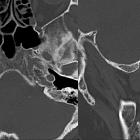

High-resolution temporal bone CT is routinely performed and may show:

- soft tissue density in the middle ear cavity

- thickened tympanic membrane

- bulging tympanic membrane

- tympanic perforation

Features seen in chronic rather than acute otitis media include:

- air-fluid level in the middle ear (effusion)

- bony erosion (less than 10%)

- adjacent sclerosis and hypopneumatisation of the mastoid